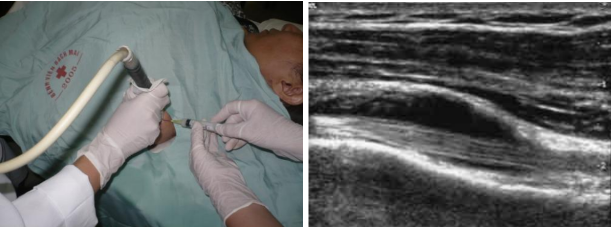

- Siêu âm xác định vị trí cần tiêm: đặt đầu dò ở lát cắt dọc qua bó dài gân cơ nhị đầu.

- Tiến hành chọc kim qua da, hướng kim đi song song với đầu dò và vuông góc với chùm tia siêu âm và đồng thời với quan sát trên màn hình, tiến kim sát tới bao gân của bó dài gân nhị đầu, khi kim tới vị trí bao gân thì tiến hành tiêm thuốc.

Hình ảnh: Tiêm gân nhị đầu dưới hướng dẫn của siêu âm